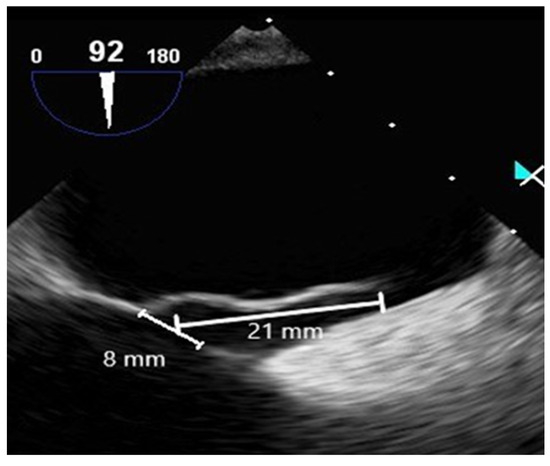

2.2.1. Cardiac Testing

2.2.3. Contrast-Enhanced Transesophageal Echocardiography